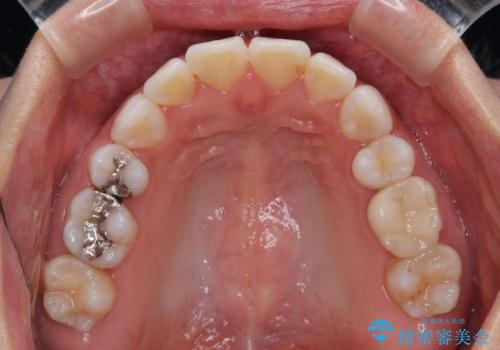

- 上下前歯の後戻りを気にして来院された患者様です。

インビザラインでの治療を希望されていて、デコボコの程度が中等度であり、安価なパッケージにて対応可能と判断されたため、インビザライン・モデレートを用いて矯正治療を行うこととしました。

インビザライン・モデレートは、製作できるアライナーの枚数に制限があるため、移動可能な量に限りがあるものの、インビザライン・ライトよりも枚数が多いため、幅広い症例に対応可能です。